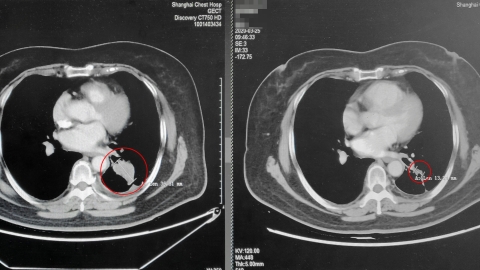

China's Approval For New Lung Cancer Drug - SHINE News

China's approval for new lung cancer drug - SHINE News www.shine.cn

lung